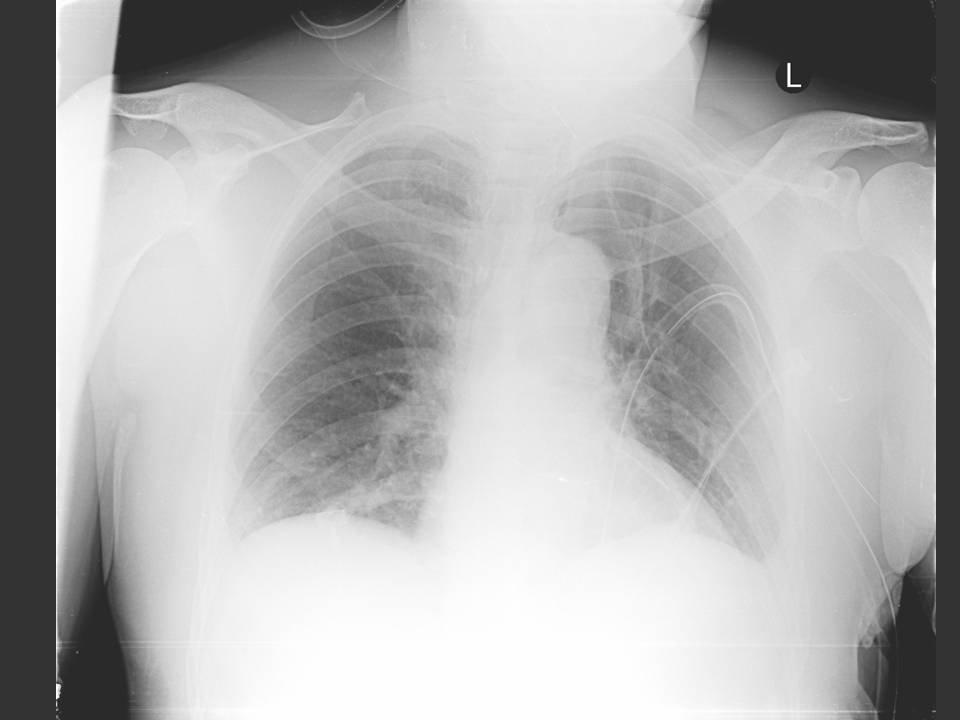

Ninety percent of spontaneous ruptures occur in the distal esophagus. Most occur on the left side just above the diaphragm, where the normal esophagus lacks serosal covering and there may be thinning of the muscularis mucosa. Seventy-five to 90% of spontaneous thoracic esophageal perforations are associated with left sided pleural effusions or hydropneumothorax, as seen in this patient (1).